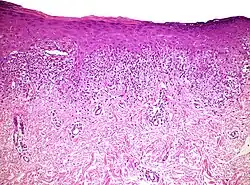

Histopathology of lichenoid drug reaction. It resembles lichen planus because of irregular epithelial hyperplasia, focal hypergranulosis, orthokeratosis, and a “saw-tooth” pattern of rete ridges.